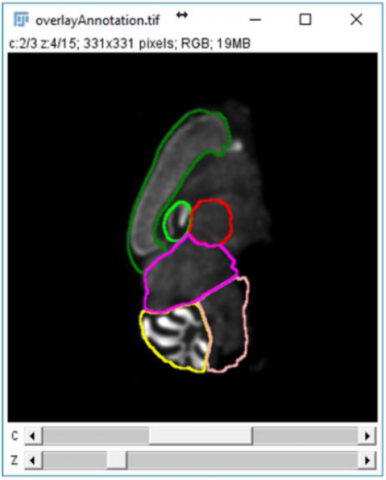

SliceMap is a FIJI/ImageJ plugin for automated brain region annotation of fluorescent brain slices. The plugin uses a reference library of pre-annotated brain slices (the brain region templates) to annotate brain regions of unknown samples. To perform the region annotation, SliceMap registers the reference slices to the sample slice (using elastic registration plugin BUnwarpJ) and uses the resulting image transformations to morph the template regions towards the anatomical brain regions of the sample. The resulting brain regions are saved as FIJI/ImageJ ROI’s (Regions Of Interest) as a single zip-file for each sample slice.